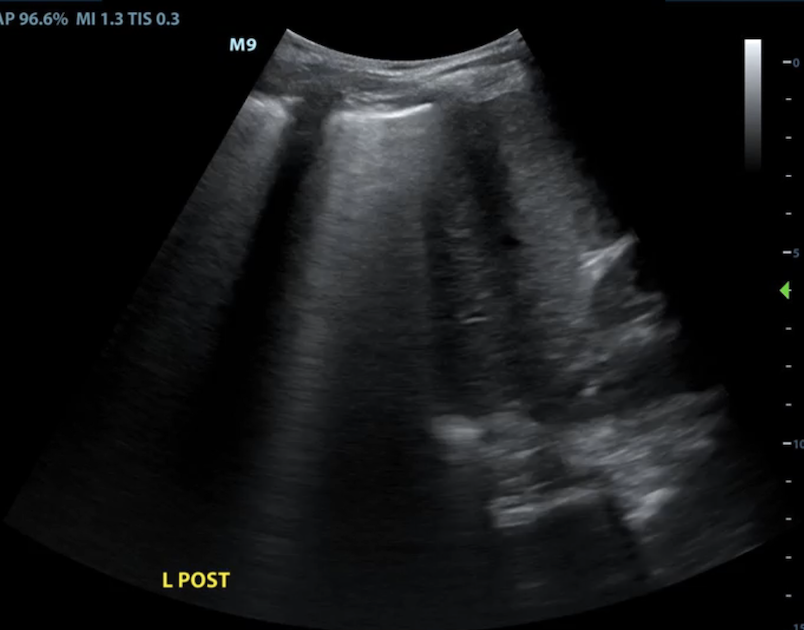

Renal and bladder ultrasound are incorporated within this curriculum to complete the evaluation of AKI and obstructive physiology at the bedside.

Participants develop a question-driven approach to renal POCUS:

• Is obstruction contributing to AKI?

• Is hydronephrosis truly present?

Emphasis is placed on avoiding common pitfalls (e.g., parapelvic cysts mimicking hydronephrosis) and building confidence in technically challenging patients.

• Renal/bladder ultrasound for obstruction, retention, and AKI phenotyping

• Bedside renal/bladder ultrasound for AKI and urinary retention